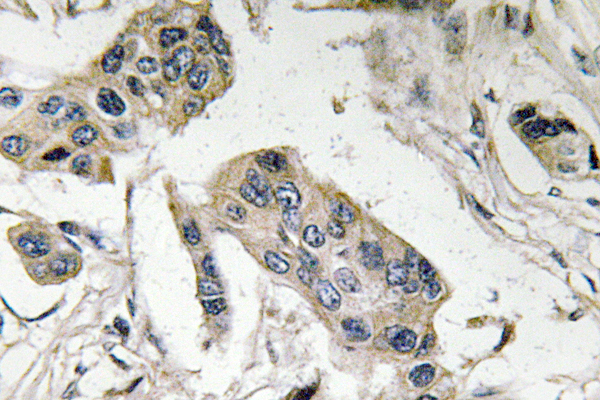

Anti-FucT-IV AntibodyA99983

ApplicationsELISA, ImmunoHistoChemistry

ReactivityHuman

Anti-ANKRD26 AntibodyA99984

ApplicationsELISA, ImmunoHistoChemistry

ReactivityHuman

Anti-ABHD12B AntibodyA99985

ApplicationsELISA, ImmunoHistoChemistry

ReactivityHuman